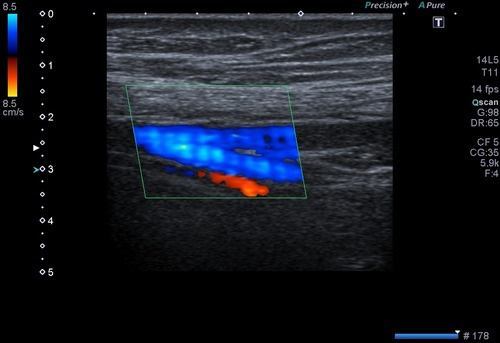

Renkli doppler incelemede gözle görülen yüzeysel yerleşimli varisler dışında kas tabakaları arasındaki derin damarlar da incelenir. Derin damarlarda problem olmaması durumunda yüzeysel yerleşimli varisler direk tedavi edilebilir.

Venöz tromboz adını verdiğimiz durum toplardamarlarda tıkanıklığa yol açan pıhtı oluşumudur. Bu durumda bacakta ısı artışı, kızarıklık ve ağrı olabilir. Bu durumda acil olarak renkli doppler ultrason inceleme yapılmalıdır.

Hangi damarlarda pıhtı oluşumu olduğu, ne kadar yer kapladığı ve ne kadar süre önce oluştuğu bu incelemeden anlaşılır.